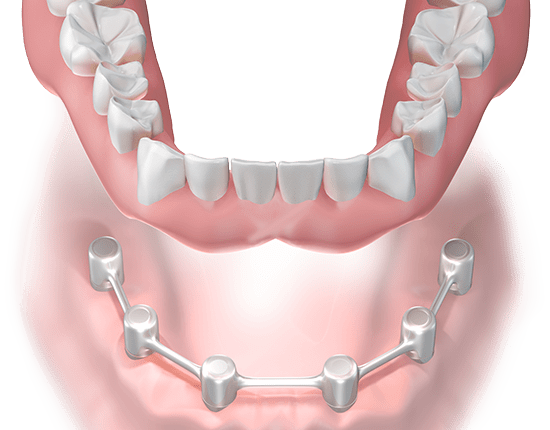

The top of your implant has a hollow area that a fastener (known as an abutment) is screwed into. This spacer protrudes from the gums and the crown is cemented on top of it. Sometimes it is possible that the distance begins to loosen from the implant, so that it loosens.

Tightening of a Loose Dental Implant Abutment However, it is more common for implants to come loose due to bruxism or gnashing of teeth. A loose abutment can usually be fixed without compromising the integrity of the implant. In some cases, the oral surgeon may remove the crown and tighten the connector.

The top of your implant has a hollow area that a fastener (known as an abutment) is screwed into. This spacer protrudes from the gums and the crown is cemented on top of it. Sometimes it is possible that the distance begins to loosen from the implant, so that it loosens.

The top of your implant has a hollow area that a fastener (known as an abutment) is screwed into. This spacer protrudes from the gums and the crown is cemented on top of it. Sometimes it is possible that the distance begins to loosen from the implant, so that it loosens.

If the small screw that connects the implant crown / abutment to the implant itself is loose, most of the time you just need to replace and tighten that screw. Conversely, if the implant crown is loosened, a simple resentment of the crown is all that is needed.

Why do implant screws loosen?

Reasons why the screw may be loose The main reason, however, is that the applied forces to the screw connection are greater than the clamping force. The phenomenon, known as preload, occurs when the screw is tightened within its elastic limits and optimizes the abutment implant joint to remain stable.

Can teeth implants loosen?

The top of your implant has a hollow area that a fastener (known as an abutment) is screwed into. This spacer protrudes from the gums and the crown is cemented on top of it. Sometimes it is possible that the distance begins to loosen from the implant, so that it loosens.